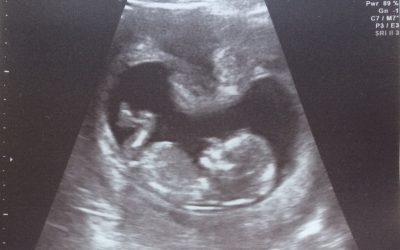

22. 11. 2021 jsme jeli na embryotransfer. Vybavuji si nádherný pocit, když jsem vše viděla na obrazovce. Naše embryjko zavedli katetrem do mé dělohy, pak jsem si 15 minut poležela, dostala jsem fotku našeho drobečka a jeli jsme domů. Všech zbylých 7 embryjek jsme nechali zmrazit. Na krevní test jsme měla jet nejdříve 13. den po transferu. To čekání bylo to nejhorší z celého IVF. Vydržela jsem nedělat si test dříve, abych nehonila nějaké duchy na testu a nebyla jsem zklamaná. 13. den vycházel na pondělí, a proto jsem se v neděli ráno rozhodla, že už nemám co ztratit a udělala si domácí test z moči ráno v 7 hodin. Okamžitě se zabarvila i druhá čárka a mně se klepaly ruce, nemohla jsem tomu uvěřit, po 6 letech negativních testů teď pozitivní. Já jsem se ale pořád držela zpátky, protože testy se mohou mýlit a raději počkám na krev. Na tu jsem jela následující den ráno a čekaly nás výsledky 1161 mlU hCG. Lékař mi ultrazvukem těhotenství potvrdil a já si doslova připadala jako Alenka v říši divů, opravdu doslova. Kdo nezažil, nepochopí. Prožívat 6 let každou ovulaci vždy s nadějí a s každou menstruací zase zklamání. A teď najednou po 1. cyklu IVF a ještě při 1. transferu to vyšlo.